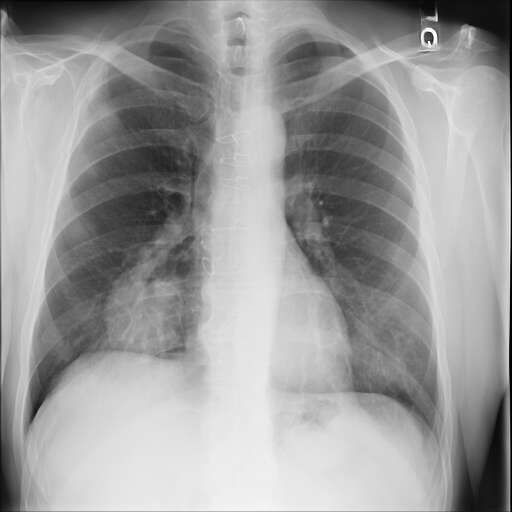

Refer to caption

(a) Original

case 1

(b) ϵ=103HWitalic-ϵsuperscript103𝐻𝑊\epsilon=10^{3}\cdot H\cdot W

(c) ϵ=102HWitalic-ϵsuperscript102𝐻𝑊\epsilon=10^{2}\cdot H\cdot W

(d) ϵ=101HWitalic-ϵsuperscript101𝐻𝑊\epsilon=10^{1}\cdot H\cdot W

(e) Original

case 2

(f) ϵ=103HWitalic-ϵsuperscript103𝐻𝑊\epsilon=10^{3}\cdot H\cdot W

(g) ϵ=102HWitalic-ϵsuperscript102𝐻𝑊\epsilon=10^{2}\cdot H\cdot W

(h) ϵ=101HWitalic-ϵsuperscript101𝐻𝑊\epsilon=10^{1}\cdot H\cdot W

(i) Original

case 3

(j) ϵ=103HWitalic-ϵsuperscript103𝐻𝑊\epsilon=10^{3}\cdot H\cdot W

(k) ϵ=102HWitalic-ϵsuperscript102𝐻𝑊\epsilon=10^{2}\cdot H\cdot W

(l) ϵ=101HWitalic-ϵsuperscript101𝐻𝑊\epsilon=10^{1}\cdot H\cdot W

(m) Original

case 4

(n) ϵ=103HWitalic-ϵsuperscript103𝐻𝑊\epsilon=10^{3}\cdot H\cdot W

(o) ϵ=102HWitalic-ϵsuperscript102𝐻𝑊\epsilon=10^{2}\cdot H\cdot W

(p) ϵ=101HWitalic-ϵsuperscript101𝐻𝑊\epsilon=10^{1}\cdot H\cdot W

Figure 2: ϵitalic-ϵ\epsilon-LDP-processed CXR images obtained with DP-GLOW.

In Fig. 1, we show four ϵitalic-ϵ\epsilon-LDP-processed CXR images of clinical cases obtained with the image domain LDP, which directly imposes the Laplace mechanism on the input image, with different privacy budgets together with the original images. Fig. 2 shows four ϵitalic-ϵ\epsilon-LDP-processed CXR images of clinical cases obtained with DP-GLOW and different privacy budgets together with the original images. In case 1 for DP-GLOW, there is decreased permeability in the bilateral hilar regions. Although this hilar opacity tends to be preserved with a larger privacy budget, the entire image is degraded when the privacy budget becomes 101HWsuperscript101𝐻𝑊10^{1}\cdot H\cdot W. A similar tendency is observed in the images of all the four cases for DP-GLOW; for example, in case 4 with ϵ=101HWitalic-ϵsuperscript101𝐻𝑊\epsilon=10^{1}\cdot H\cdot W, the lung opacity suggesting pneumonia in the right lower lung field is well preserved, while the entire image is degraded.